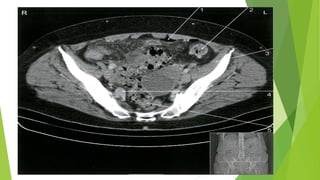

CT abdomen and pelvis with IV contrast

Indications

• Preferred initial imaging modality for suspected diverticulitis

• Diagnostic confirmation in patients with no prior imaging studies

• Staging the severity of diverticulitis

Supportive findings

Colonic outpouching

Signs of inflammation

• Bowel wall thickening > 3 mm

• Peridiverticular mesenteric fat stranding

Complications may also be identified

• Peridiverticular abscess: hypodense collections with peripheral contrast enhancement

• Diverticular perforation: pneumoperitoneum

• Intestinal obstruction: dilated intestinal loops with multiple air-fluid levels